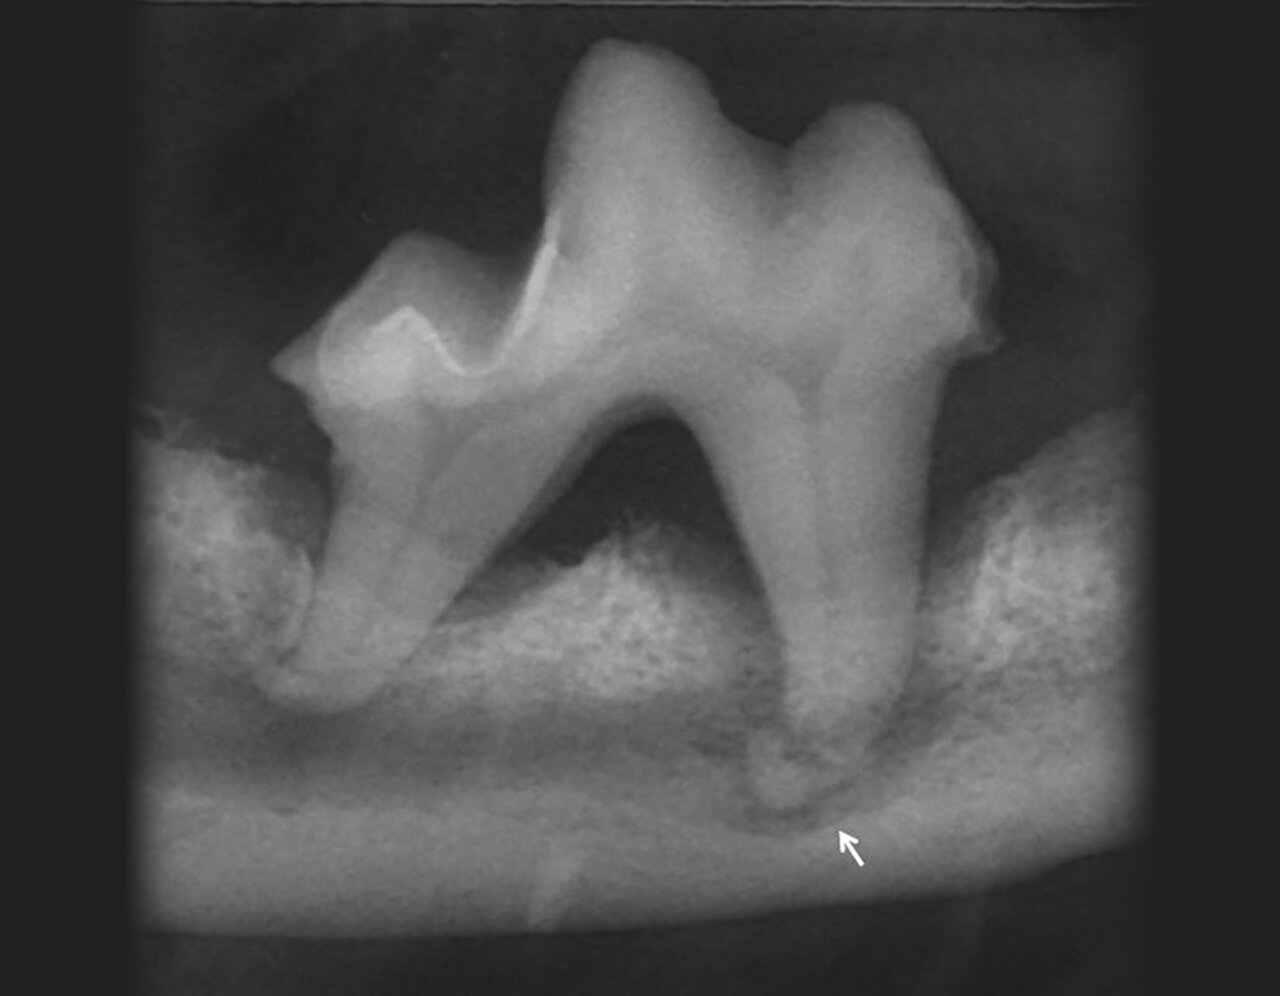

La caries es una desmineralización del diente como consecuencia de los ácidos producidos por la fermentación de los carbohidratos por parte de la placa bacteriana. Esta desmineralización y destrucción del esmalte y la dentina ocasionan pérdida de la densidad en la zona afectada del diente (imagen 12).

Aunque la caries puede afectar a cualquier diente, en la mayoría de las ocasiones, en los perros, aparece de forma más frecuente en la superficie oclusal de la cara distal del primer molar mandibular y del primer molar maxilar. Estos dientes son particularmente propensos a la caries debido a sus características anatómicas (presencia de fosas y surcos).

A nivel radiológico, la lesión se manifiesta como una imagen radiolúcida de bordes irregulares. La línea delimitante de la lesión dependerá de la etapa del proceso, en un principio se trata de una zona radiolúcida que se extiende desde la superficie dental del esmalte profundizando hacia la dentina y, una vez que la caries alcanza la dentina, la lesión se extiende rápidamente bajo el esmalte, convirtiéndose en mucho más grande de lo que sospechamos por inspección visual.

La profundidad de la lesión, su proximidad a la pulpa, así como las posibles lesiones periapicales, solo pueden valorarse mediante radiografía.